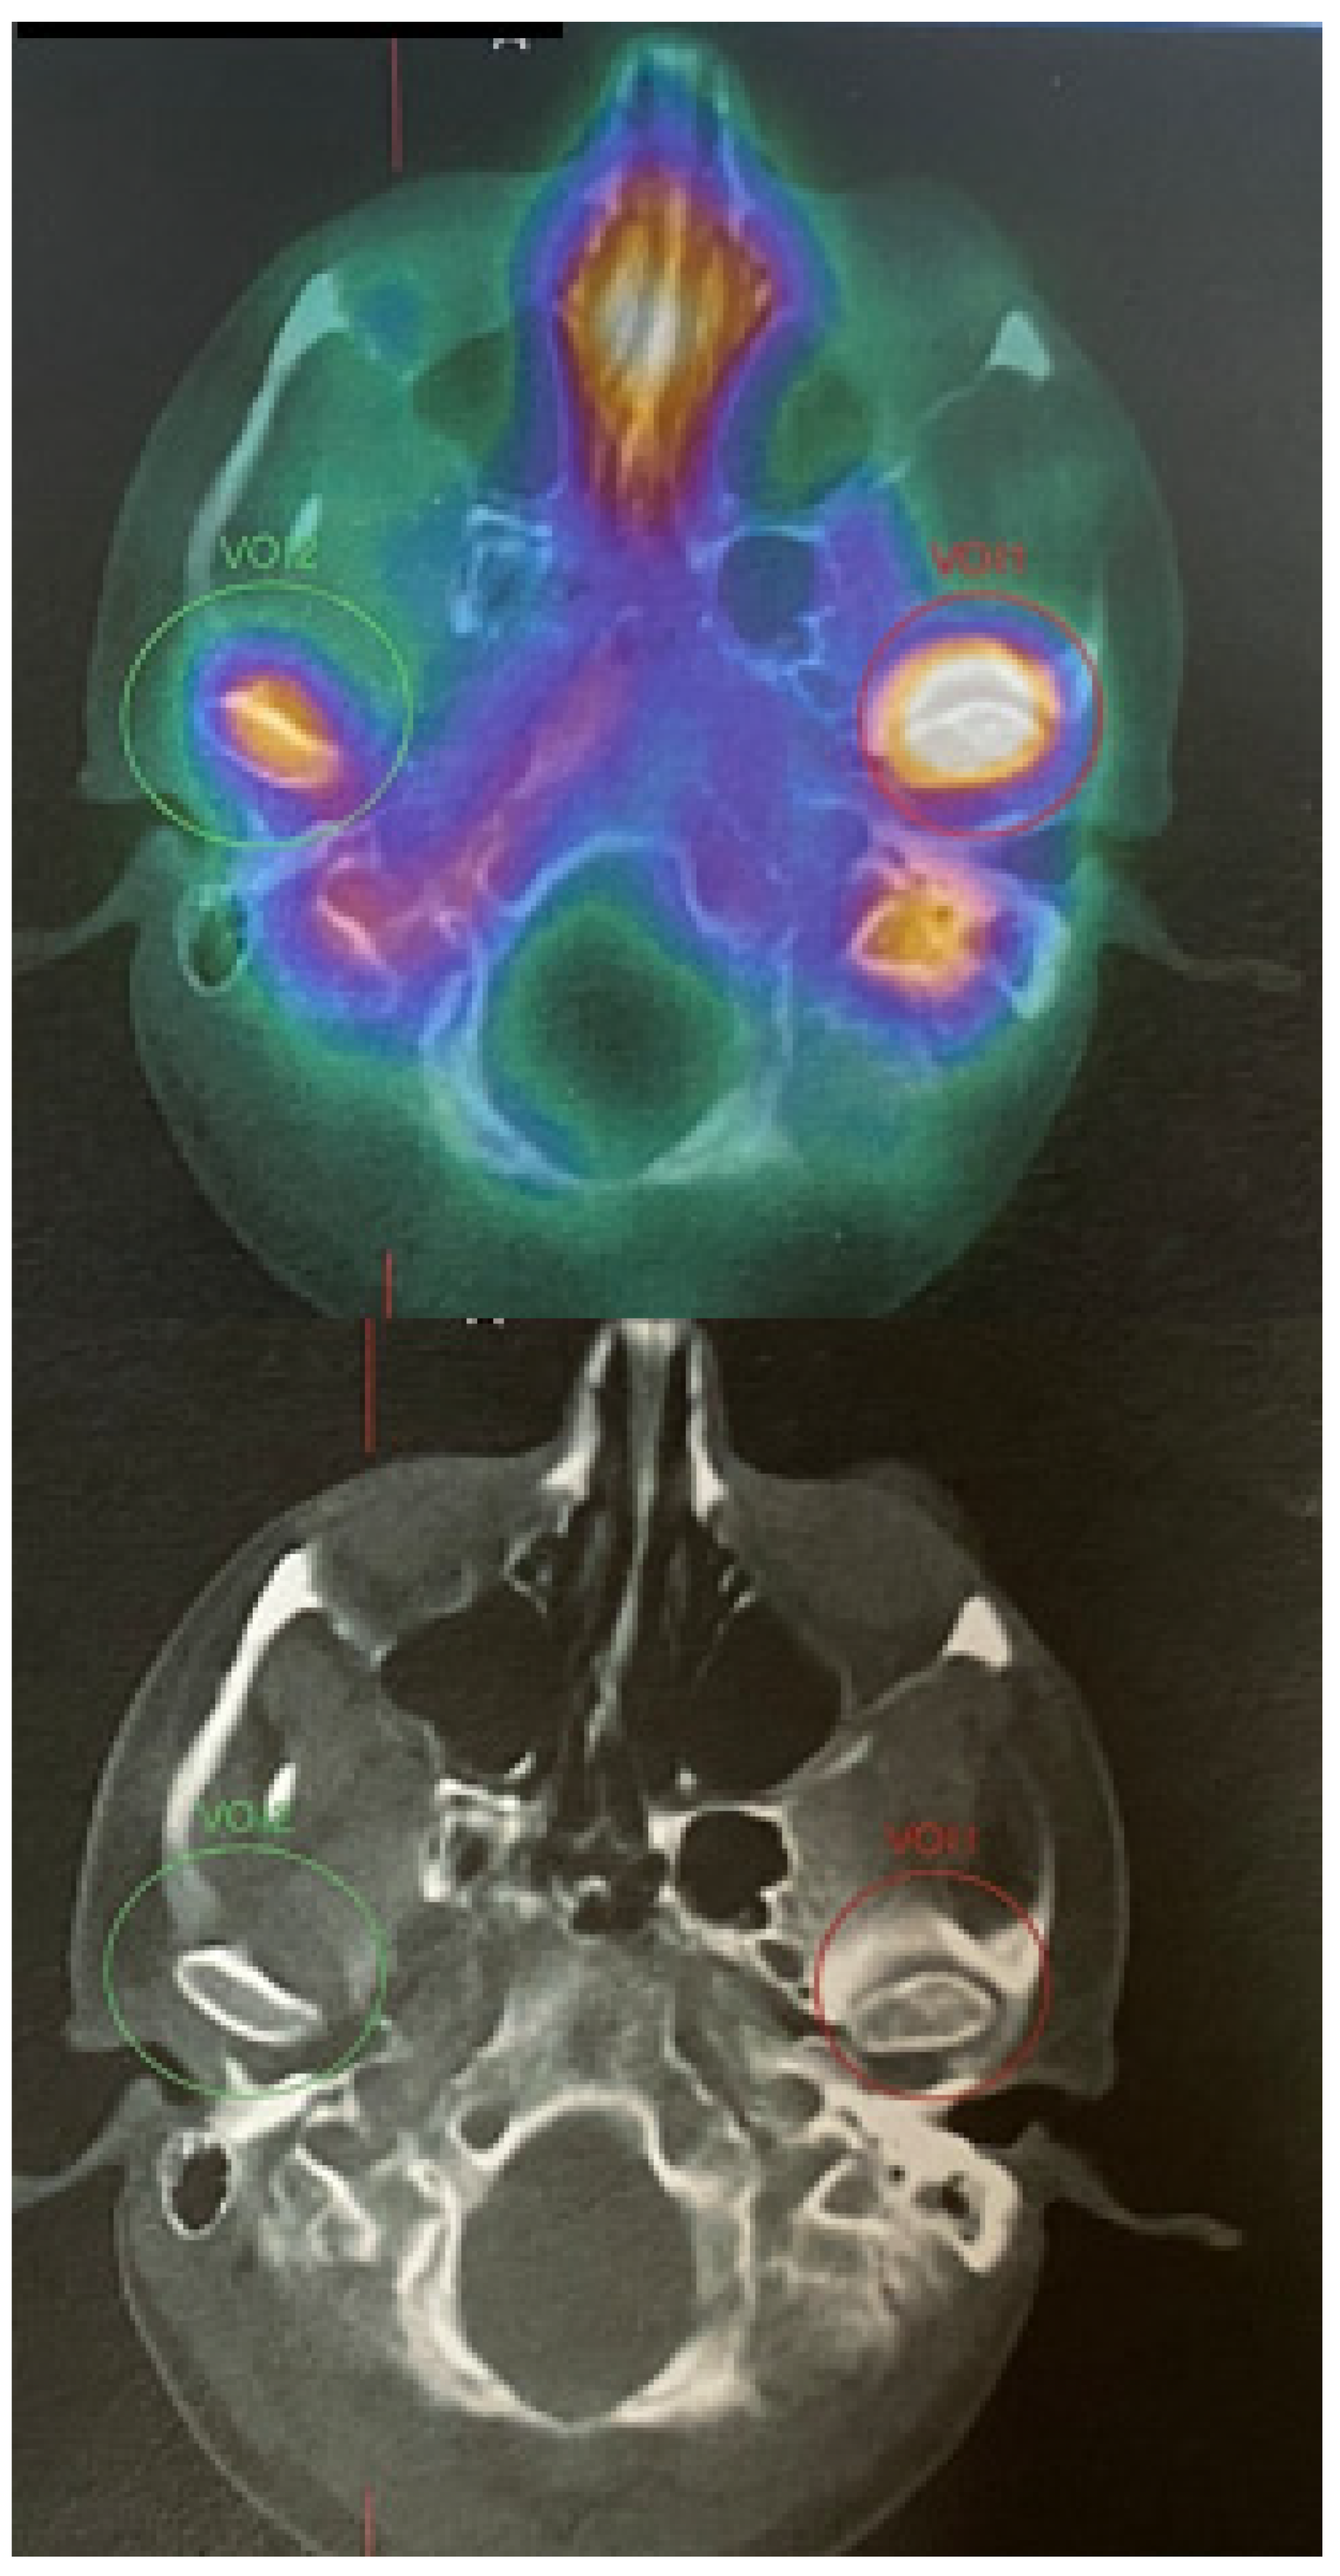

SPECT-CT of the facial skeleton revealed an atypical, extensive, and progressive accumulation of growth in the left mandibular condyle head. The MDP Tc99m (Technetium 99m methylene diphosphonate) is quite important because any accumulation within the affected condyle might either mean inflammation, bone growth, abnormal bone growth, bone tumor, joint overload, some atypical tumors/bone metaplasia, or other findings when the craniofacial skeleton is evaluated. Some authors suggest that the differences in radio uptake of more than 10–15% might suggest growing condylar hyperplasia; however, a full clinical, radiological and SPECT comparison should be drawn at least two times in 4–6 months’ time to compare their features. SPECT-CT alone is not enough to confirm any UCH pathology; therefore, a detailed CT/CBCT/LDCT evaluation and clinical patient examination can greatly influence the future final identification of the disease. Many authors emphasize that SPECT is a very important diagnostic tool and should be always performed in cases of any skeletal asymmetries, especially mandibular asymmetry [4,5]. Abbreviations: UCH—unilateral condylar hyperplasia; CT/LDCT—computed tomography/low-dose computed tomography; green circle–negative growth; red circle–proggresive bone growth in SPECT.